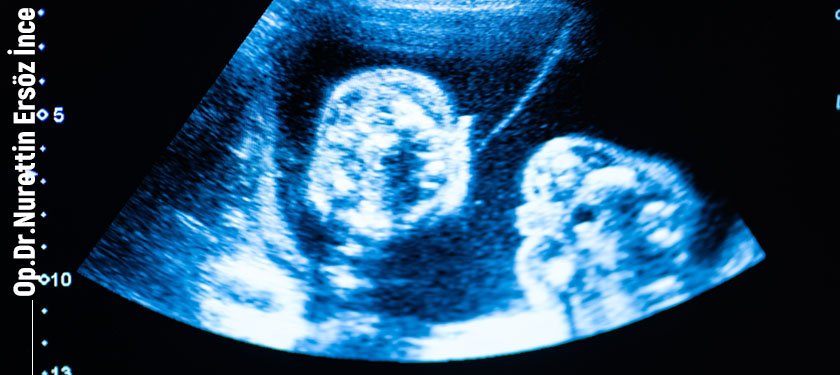

A. Ultrason

Ultrason, çocuğun cinsiyetinin belirlenebilmesi için kullanılan en yaygın yöntemdir. Gebelikte 12. haftadan sonra vajinal ultrason ile ya da 16. haftadan sonra karından bakılabilen ultrasonla çocuğun cinsiyeti tespit edilebilir.

Elbette, çocuğun cinsiyetinin tespitinde çocuğun ultrason esnasında bulunduğu pozisyon, ultrasonu yapan doktorun tecrübesi ve kullanılan ultrason aletinin kalitesi gibi faktörler de sonucun güvenilirliği bakımından son derece önemlidir.